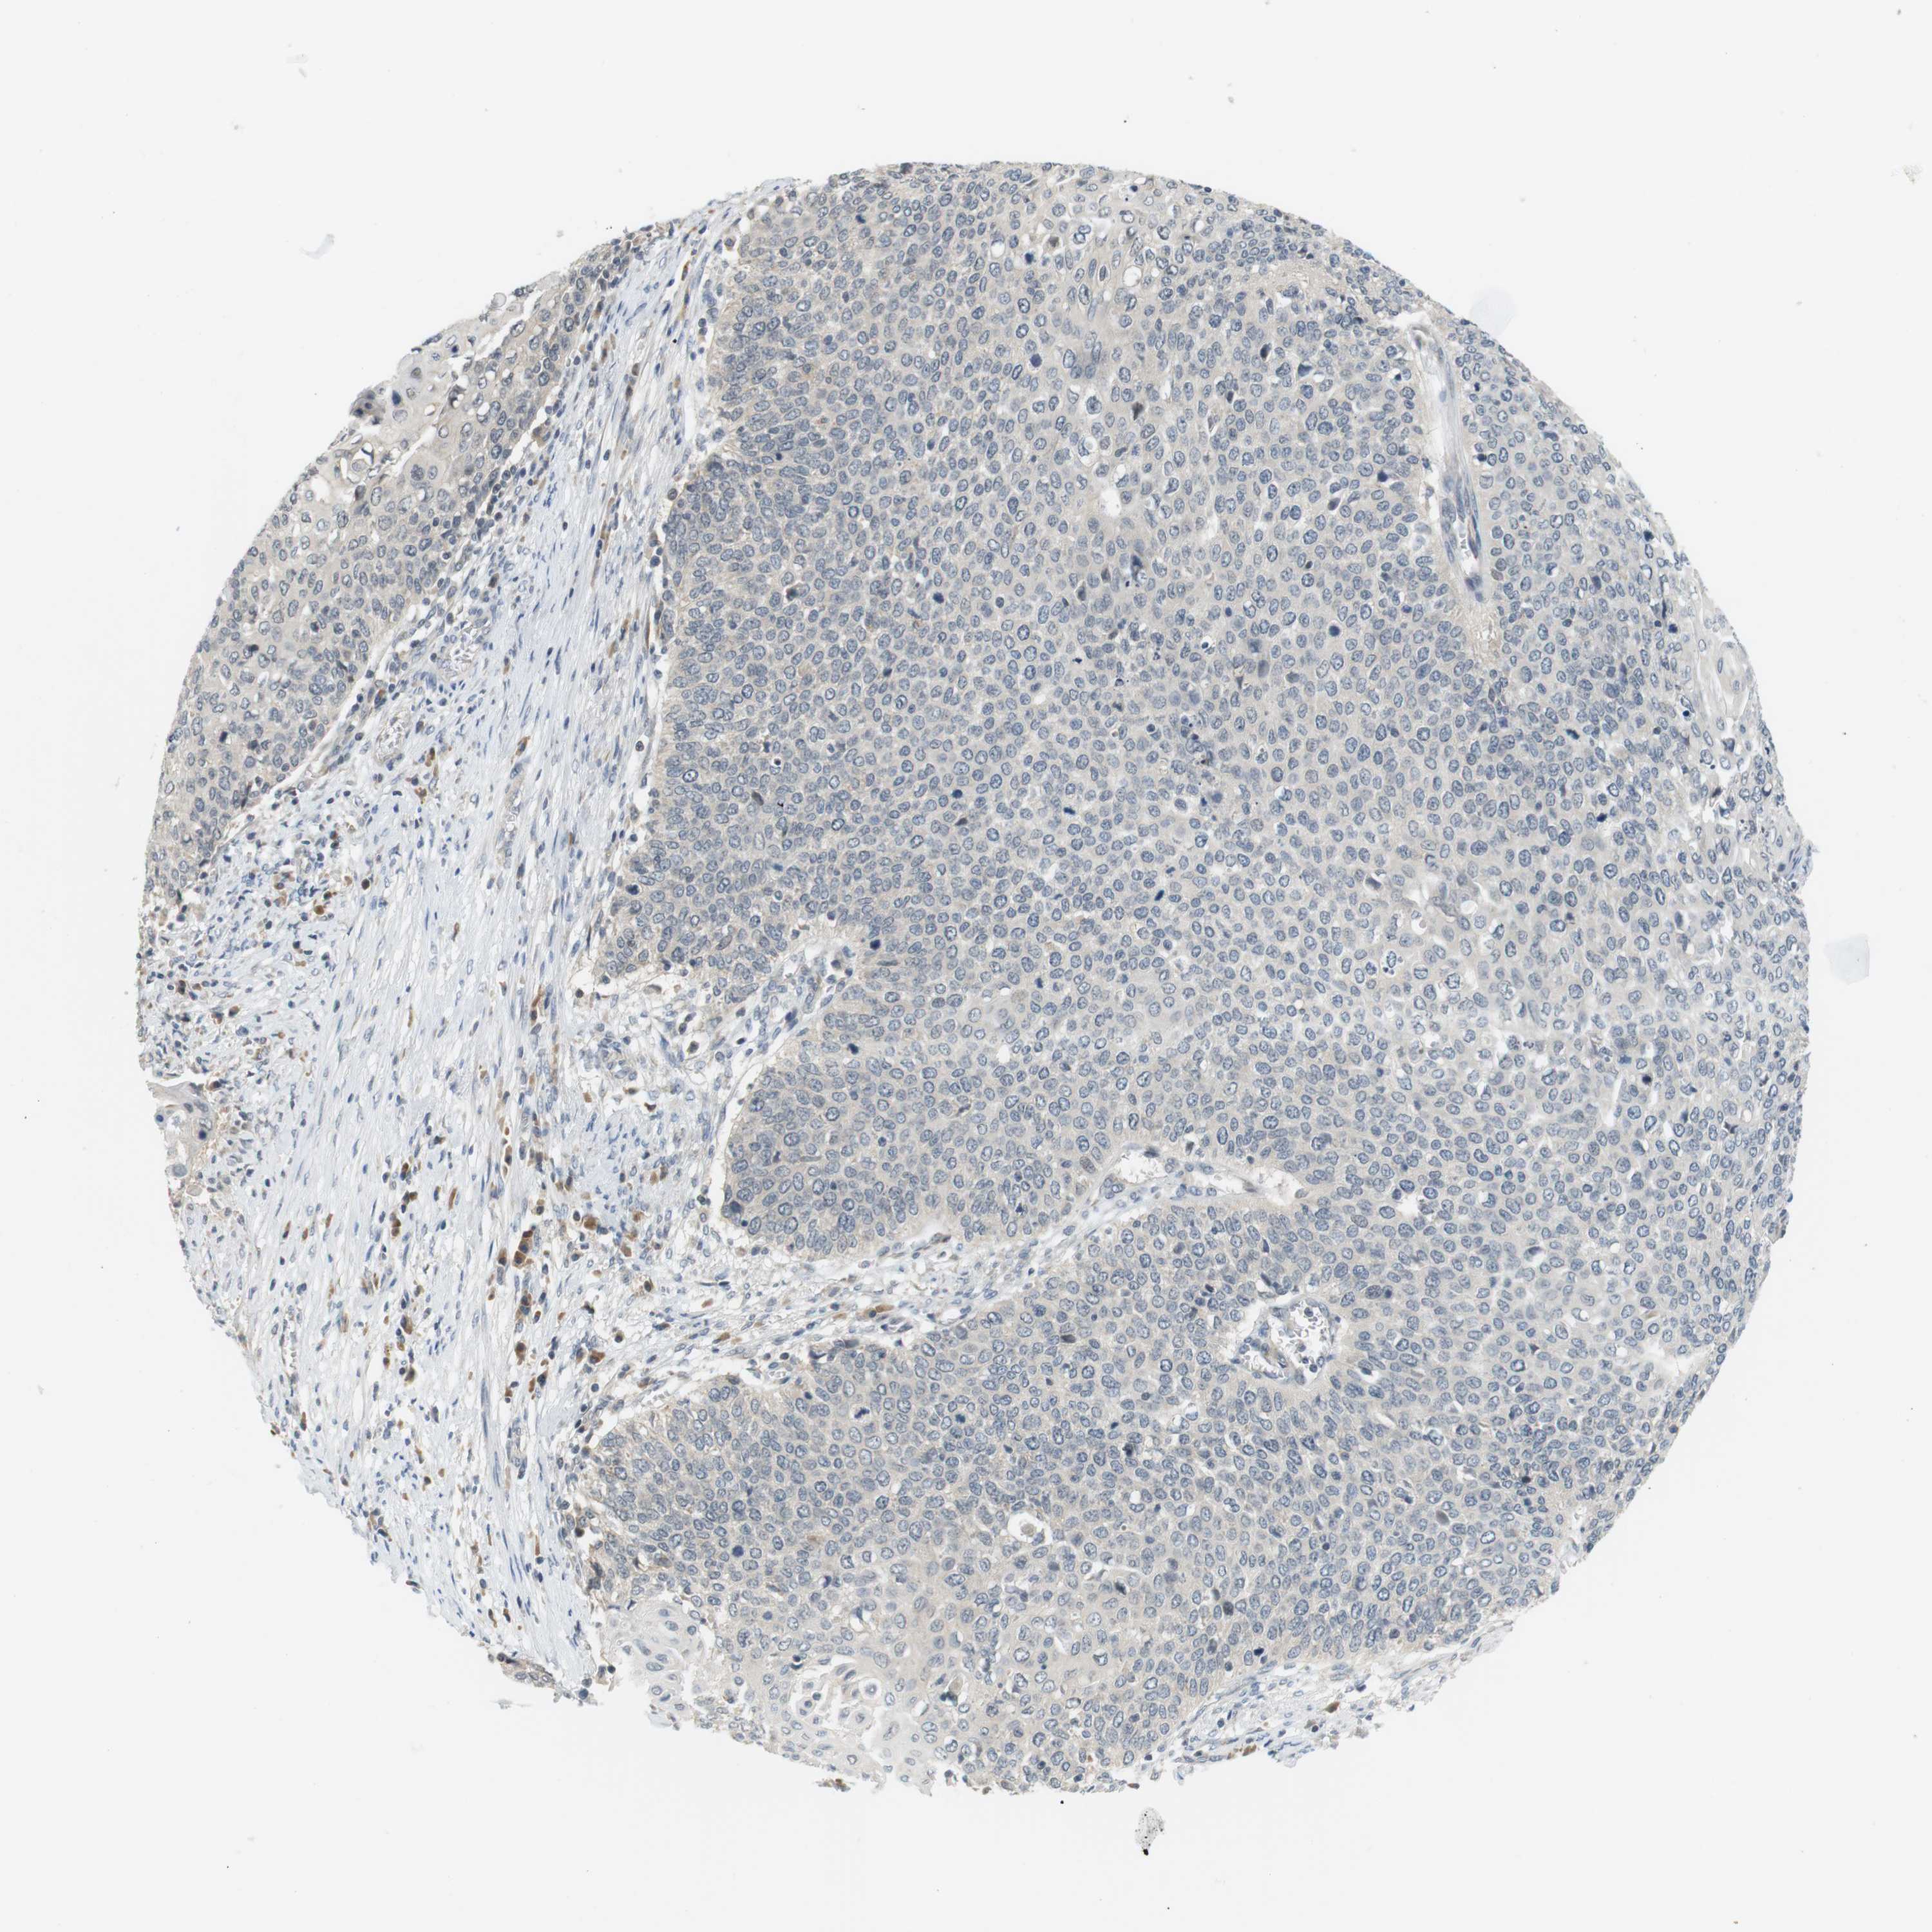

CERVICAL CANCER - Protein expressioni

A mouse-over function shows sample information and annotation data. Click on an image to view it in a full screen mode. Samples can be filtered based on level of antibody staining by selecting one or several of the following categories: high, medium, low and not detected. The assay and annotation is described here.

Note that samples used for immunohistochemistry by the Human Protein Atlas do not correspond to samples in the TCGA dataset.

Antibody stainingi

Antibody staining in the annotated cell types in the current human tissue is reported as not detected, low, medium, or high, based on conventional immunohistochemistry profiling in selected tissues. This score is based on the combination of the staining intensity and fraction of stained cells.

Each image is clickable and will lead to virtual microscopy that enables deeper exploration of all samples and also displays staining intensity scores, fraction scores and subcellular localization as well as patient and tissue information for each sample.

Antibody HPA015719

Antibody CAB025894

Squamous cell carcinoma, NOS

Adenocarcinoma, NOS